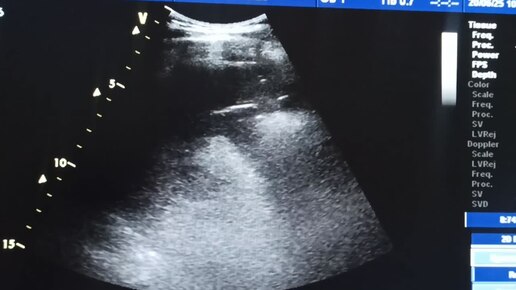

УЗИ начинаюшим врачам: Хвост поджелудочной железы из селезеночного доступа.